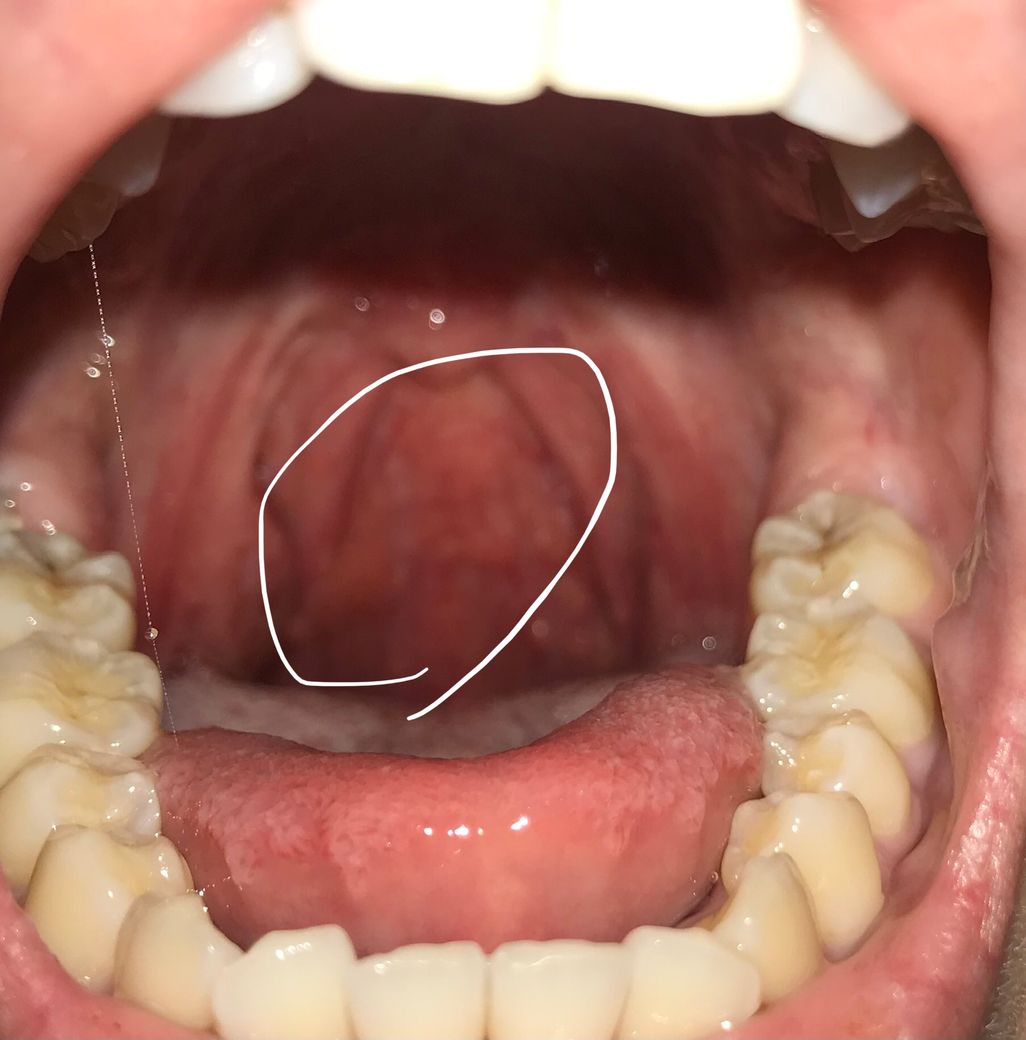

목구멍을 보니까 이렇게 되어있는데 뭔 문제가 있는건가요?

저렇게 오돌토돌 나읶는건 정상인거 아닌데 그런 오돌토돌 느낌 보다는 좀 더 크게 부은 느낌으로 나 있어요 ㅠㅠ 목이 부은건가요???

이는 Cobble-stone appearance 라고 하여서 만성 비염으로 인한 후비루가

지속될 때 목 뒤가 붓고 자갈밭 처럼 변하는 모습을 보이게 됩니다.

이를 통해 만성 비염이 있음을 간접적으로 확인할 수 있습니다.

특별히 이물감이나 통증이 없으시다면 경과관찰이 가능하겠으나 불편감이 있으시다면 이비인후과에 내원하시어 내시경을 통해 정확히 확인을 해보시는 것이 좋겠습니다.